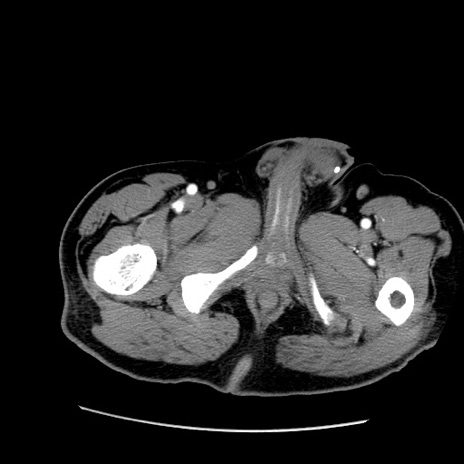

症例22(横断像)

【症例】50歳代男性

【主訴】腹痛

【現病歴】AVMからの被殻出血のため回復期リハ病棟入院中。 本日午後3時頃急に下腹部痛が出現した。

【既往歴】AVM、被殻出血、虫垂炎、高血圧

【身体所見】意識晴明、左半身不全麻痺、会話の理解は良好、36.5°C、腹部:膨隆、全体に板状硬、下腹部正中に圧痛点あり、反跳痛-、筋性防御不明、右下腹部にope scar

【データ】WBC 9400、CRP 0.06